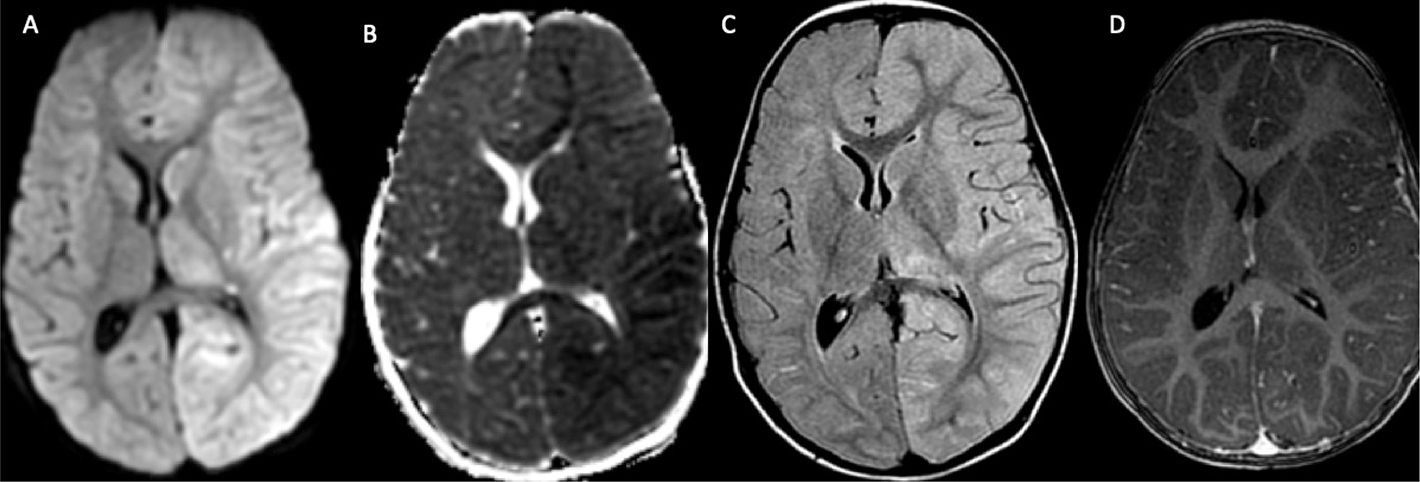

Fig 8

Figure 8. An 18-year-old male who presented with intractable headache found to have left vein of Labbe thrombosis and hemorrhagic venous infarct. DWI (A) and associated ADC (B) demonstrates associated vasogenic and cytotoxic edema. Noncontract T1-weighted image (C) shows high signal within the left vein of Labbe (white arrowhead) with associated filling defect on contrast enhanced study (white arrow) (D). No underlying vascular malformation or mass was identified. T2-weighted MRI (E) demonstrates a left posterior temporal hematoma with associated edema. Noncontrast axial CT image (F) demonstrates parenchymal hemorrhage with hyperdensity within the vein of Labbe (black arrow).